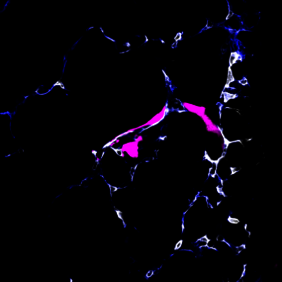

Um sich im Körper zu verbreiten, nutzen Krebszellen die Blut- oder Lymphbahnen. Wissenschaftler im DKFZ und in der Universität Heidelberg haben nun ein Verfahren entwickelt, um bei Mäusen das Verhalten wandernder Krebszellen unmittelbar bei Ankunft im metastatischen Organ – in diesem Fall der Lunge – zu beobachten.

Dabei entdeckte das Team um die beiden Erstautoren Moritz Jakab und Ki Hong Lee, dass manche Tumorzellen, sobald sie im Zielorgan angekommen sind, aus dem Blutgefäß austreten und in einen Ruhezustand fallen. Andere Krebszellen dagegen fangen direkt im Blutgefäß an, sich zu teilen und zur Metastase auszuwachsen.

Diese Entscheidung wird von den Endothelzellen gesteuert, die alle Blutgefäße von innen auskleiden. Sie schütten Faktoren des Wnt-Signalwegs aus, die den Austritt der Tumorzellen aus dem Blutgefäß fördern und damit den Ruhezustand einleiten. Schalteten die Forscher die Wnt-Faktoren aus, kam es nicht mehr zur Latenz.